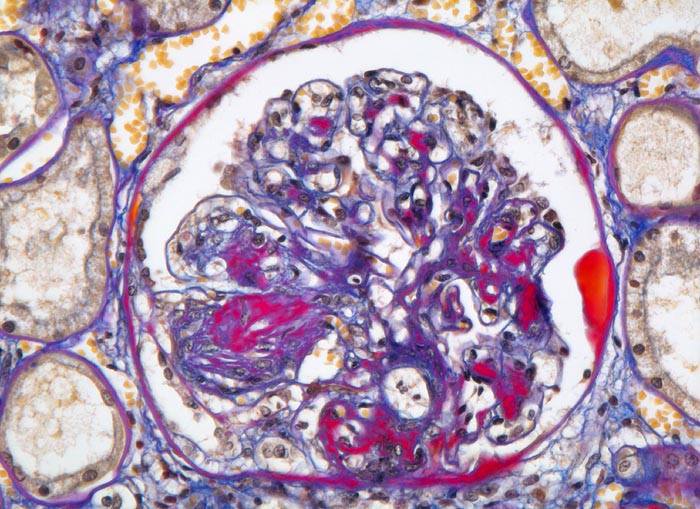

Im allgemeinen ist die Niere infolge von Glomerulumhypertrophie und Tubulushyperplasie vergrössert und derb, die Oberfläche ist granuliert. Bei schwerer Atherosklerose und fortgeschrittener Niereninsuffizienz kann die Niere auch normal gross oder verkleinert sein. Die Kombination von nodulärer Glomerulosklerose, hyalinen Schlingenkappen (=Proteinthromben in den Glomerulumschlingen (> 1916)) oder Kapseltropfen (> 1907) und Arteriolosklerose in Vas afferens und efferens ist beweisend für eine diabetische Nephropathie. Jede einzelne Läsion für sich genommen ist aber unspezifisch. Eine noduläre Glomerulosklerose kann auch vorkommen bei membranoproliferativer Glomerulonephritis (> 2652), Leichtkettenglomerulopathie oder Amyloidose (> 2019). Der nodulären Glomerulosklerose geht bei Diabetikern eine diffuse Glomerulosklerose (> 1906) voraus. Dabei zeigen die glomerulären Basalmembranen und das Mesangium eine progrediente gleichförmige Verbreiterung. Bei der nodulären und diffusen Glomerulosklerose handelt es sich aber wahrscheinlich um zwei pathogenetisch unterschiedliche, sich überlagernde Krankheitsbilder. Typisch bei Diabetikern ist im Unterschied zur arteriellen Hypertonie die Arteriolosklerose von Vas afferens und efferens (> 1911) und oft auch der Vasa recta. Intrarenale Arterien können eine Atherosklerose mit Atheromen zeigen. Subendotheliale Proteinablagerungen teilweise mit Verschluss der Glomerulumschlingen (Schlingenkappen) und knotige Proteinablagerungen in der Bowman'schen Kapselbasalmebran (Kapseltropfen) gehören zu den sogenannten exsudativen Läsionen (> 1919) (> 1920) der diabetischen Nephropathie und führen zu Synechien sowie zur globalen Glomerulosklerose. Gleichzeitig mit den Glomerulumveränderungen treten tubuläre Basalmembranverbreiterungen auf, später eine Tubulusatrophie und interstitielle Fibrose mit Begleitentzündung. Auch die Basalmembranen der peritubulären Kapillaren sind verdickt.

• Verbreiterung des Mesangiums mit Ausbildung von Knoten(noduläre Glomerulosklerose).

• Exsudative Läsionen: Hyaline Schlingenkappen (Proteinthromben in Glomerulumschlingen, im virtuellen Präparat nicht sichtbar) und Kapseltropfen (Proteinablagerungen im Bowman’schen Kapselraum).

• Arteriolosklerose von Vas afferens und efferens (Gefässwandhyalinose durch Ablagerung von Plasmaproteinen und Lipiden in der Gefässwand).